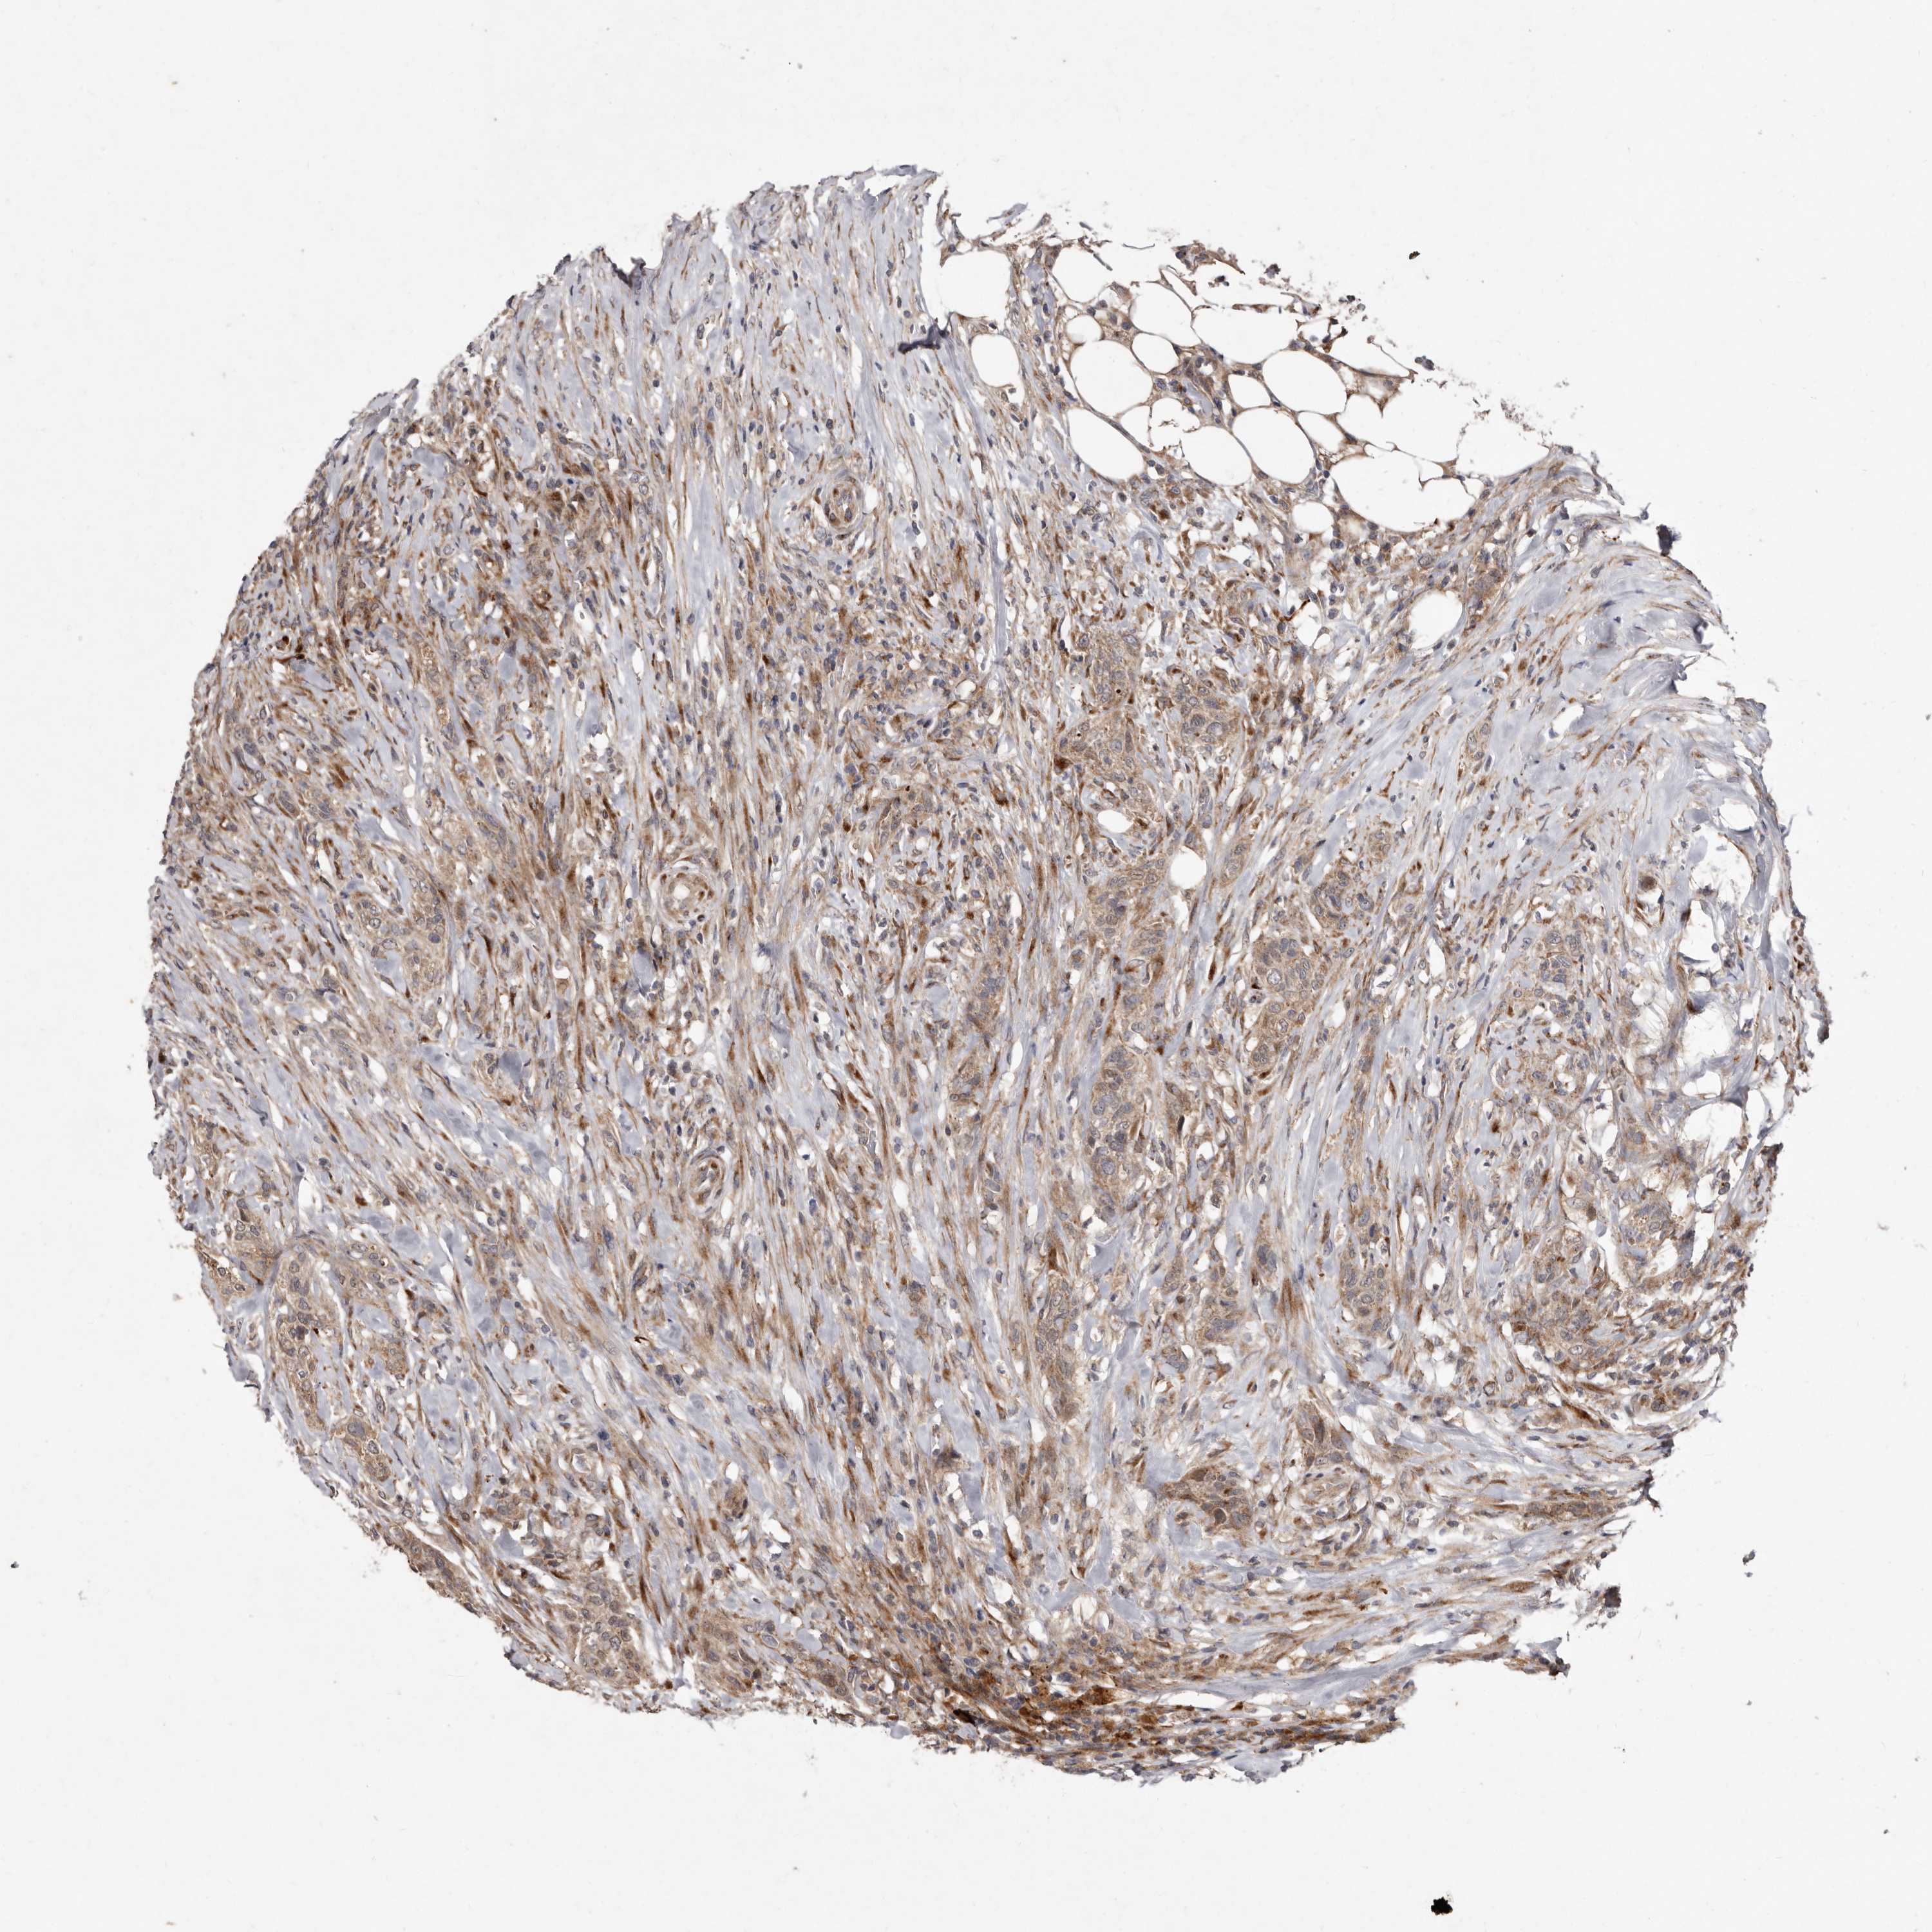

UROTHELIAL CANCER - Protein expressioni

A mouse-over function shows sample information and annotation data. Click on an image to view it in a full screen mode. Samples can be filtered based on level of antibody staining by selecting one or several of the following categories: high, medium, low and not detected. The assay and annotation is described here.

Note that samples used for immunohistochemistry by the Human Protein Atlas do not correspond to samples in the TCGA dataset.

Antibody stainingi

Antibody staining in the annotated cell types in the current human tissue is reported as not detected, low, medium, or high, based on conventional immunohistochemistry profiling in selected tissues. This score is based on the combination of the staining intensity and fraction of stained cells.

Each image is clickable and will lead to virtual microscopy that enables deeper exploration of all samples and also displays staining intensity scores, fraction scores and subcellular localization as well as patient and tissue information for each sample.

Antibody HPA028476

Antibody HPA028486

Antibody HPA028563

Staining

High

Medium

Low

Not detected

Intensity

Strong

Moderate

Weak

Negative

Quantity

>75%

75%-25%

<25%

None

Location

Nuclear

Cytoplasmic/membranous

Cytoplasmic/membranous,nuclear

Urothelial carcinoma, Low grade

Urothelial carcinoma, High grade